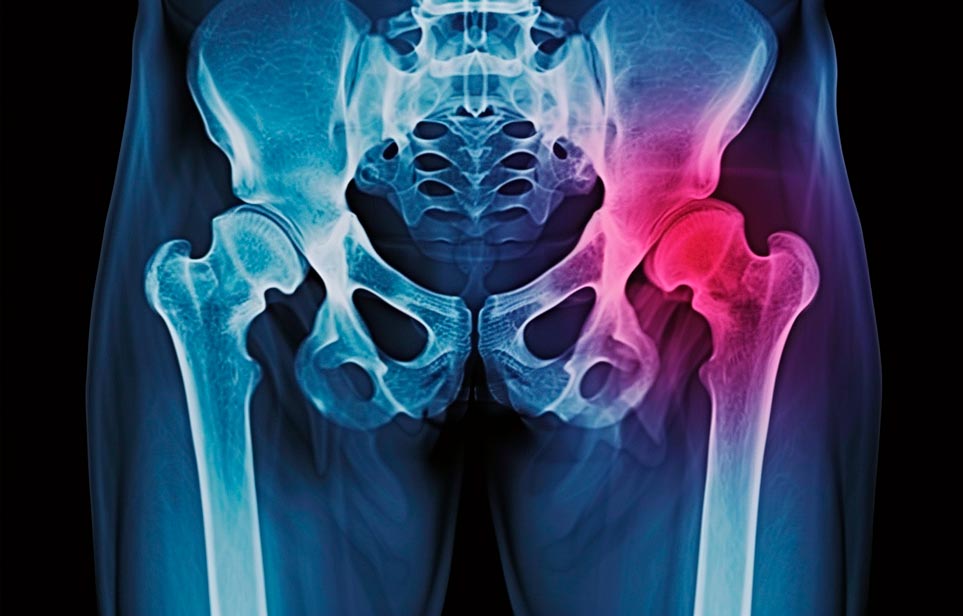

Реабилитация пожилых после перелома шейки бедра в Перми

Такая травма в большей части случаев возникает у граждан преклонного возраста. При её появлении на протяжении длительного времени сохраняются болевые и неприятные ощущения в области паха, при которых серьёзно ухудшается качество жизни, возникает множество последствий для его жизни и здоровья.

По какой симптоматике можно определить перелом шейки бедра

- Визуально повреждённая нога сокращается на несколько сантиметром из-за сокращения мышц.

- Стопа выворачивается наружу.

- В лежачем положении человек не может поднять ногу.

При такой симптоматике важно незамедлительно обращаться к специалистам для получения всей необходимой помощи, терапии и восстановления после перелома шейки бедра. Если не оказать помощи старику, то это приведёт к гноению, инвалидности, иным видам осложнений.